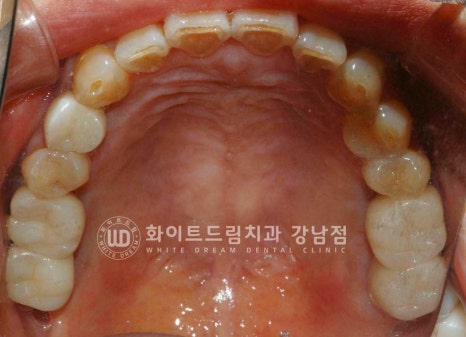

환자분의 치료 전/후 구내 사진입니다.

동일 인물이며 동일 환경에서 촬영되었습니다.

23.03.07 - 23.09.26

식립된 임플란트들이 상실된 치아의 기능을 정상적으로 이행함을 확인하며

치료를 마무리하게 되었습니다.